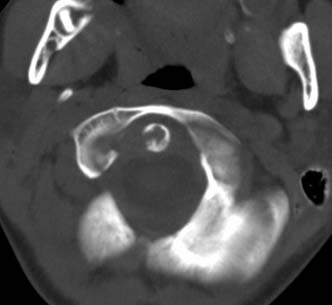

标题: PED0678:男,10岁,寰枢椎平扫。

患者在校与同龄孩子打闹后(据家长说被拳击中颈部)出现颈部不适30分钟后入院检查,来时脖子歪斜。请大家看看枢椎齿状突及寰枢关节有问题吗?(3mm层厚断层扫描)。